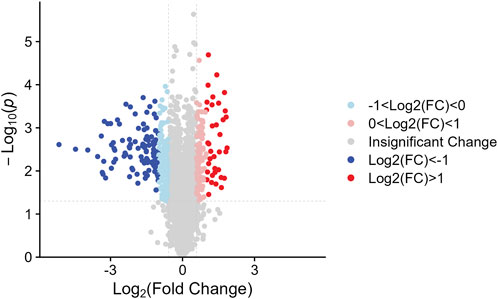

We identified the sum of 24,160 peptides after conducting a TMT-based proteomic (Supplementary Table S1). According to the filter conditions, 373 differentially expressed proteins (DEPs) in NDSTB and DSTB samples were present in Figure 3, extracted from 5033 identified proteins (Supplementary Table S2, S3). Furthermore, we also demonstrated 137 upregulated proteins (log2FC ≤ −1) and 236 downregulated proteins (log2FC > 1, p < 0.05) between the NDSTB and DSTB groups.

Figure 3. Two groups gomparison: Differential analysis showed that 373 were differentially expressed between the two groups with 236 downregulated proteins (log2FC ≤ −1) and 137 upregulated proteins (log2FC > 1, p < 0.05).